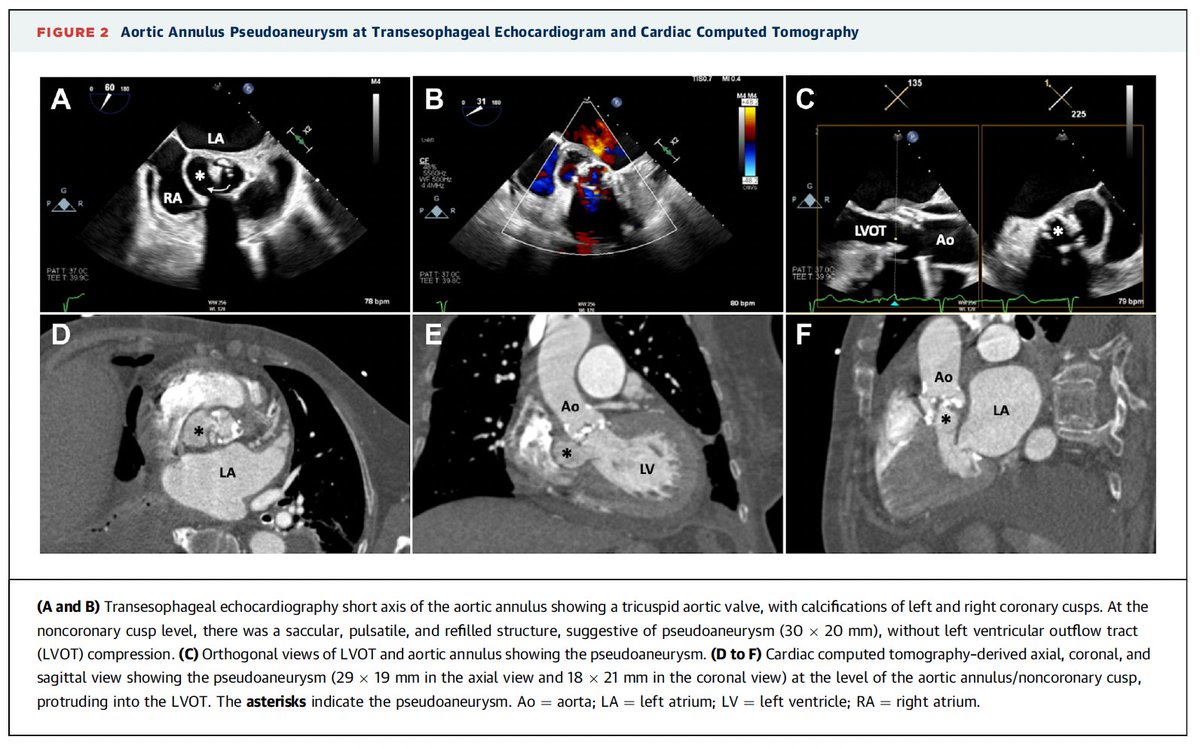

Importance of multimodality imaging in patients with severe AS and uncommon findings: Successful TAVR in Patient With Aortic Annulus Pseudoaneurysm After BAV @jaccjournals https://t.co/mekO3AR7Td @belmontemarta1 @KBerbeis @EGallinoro @Serena_Caglioni @EAPCIPresident @EricWyffels